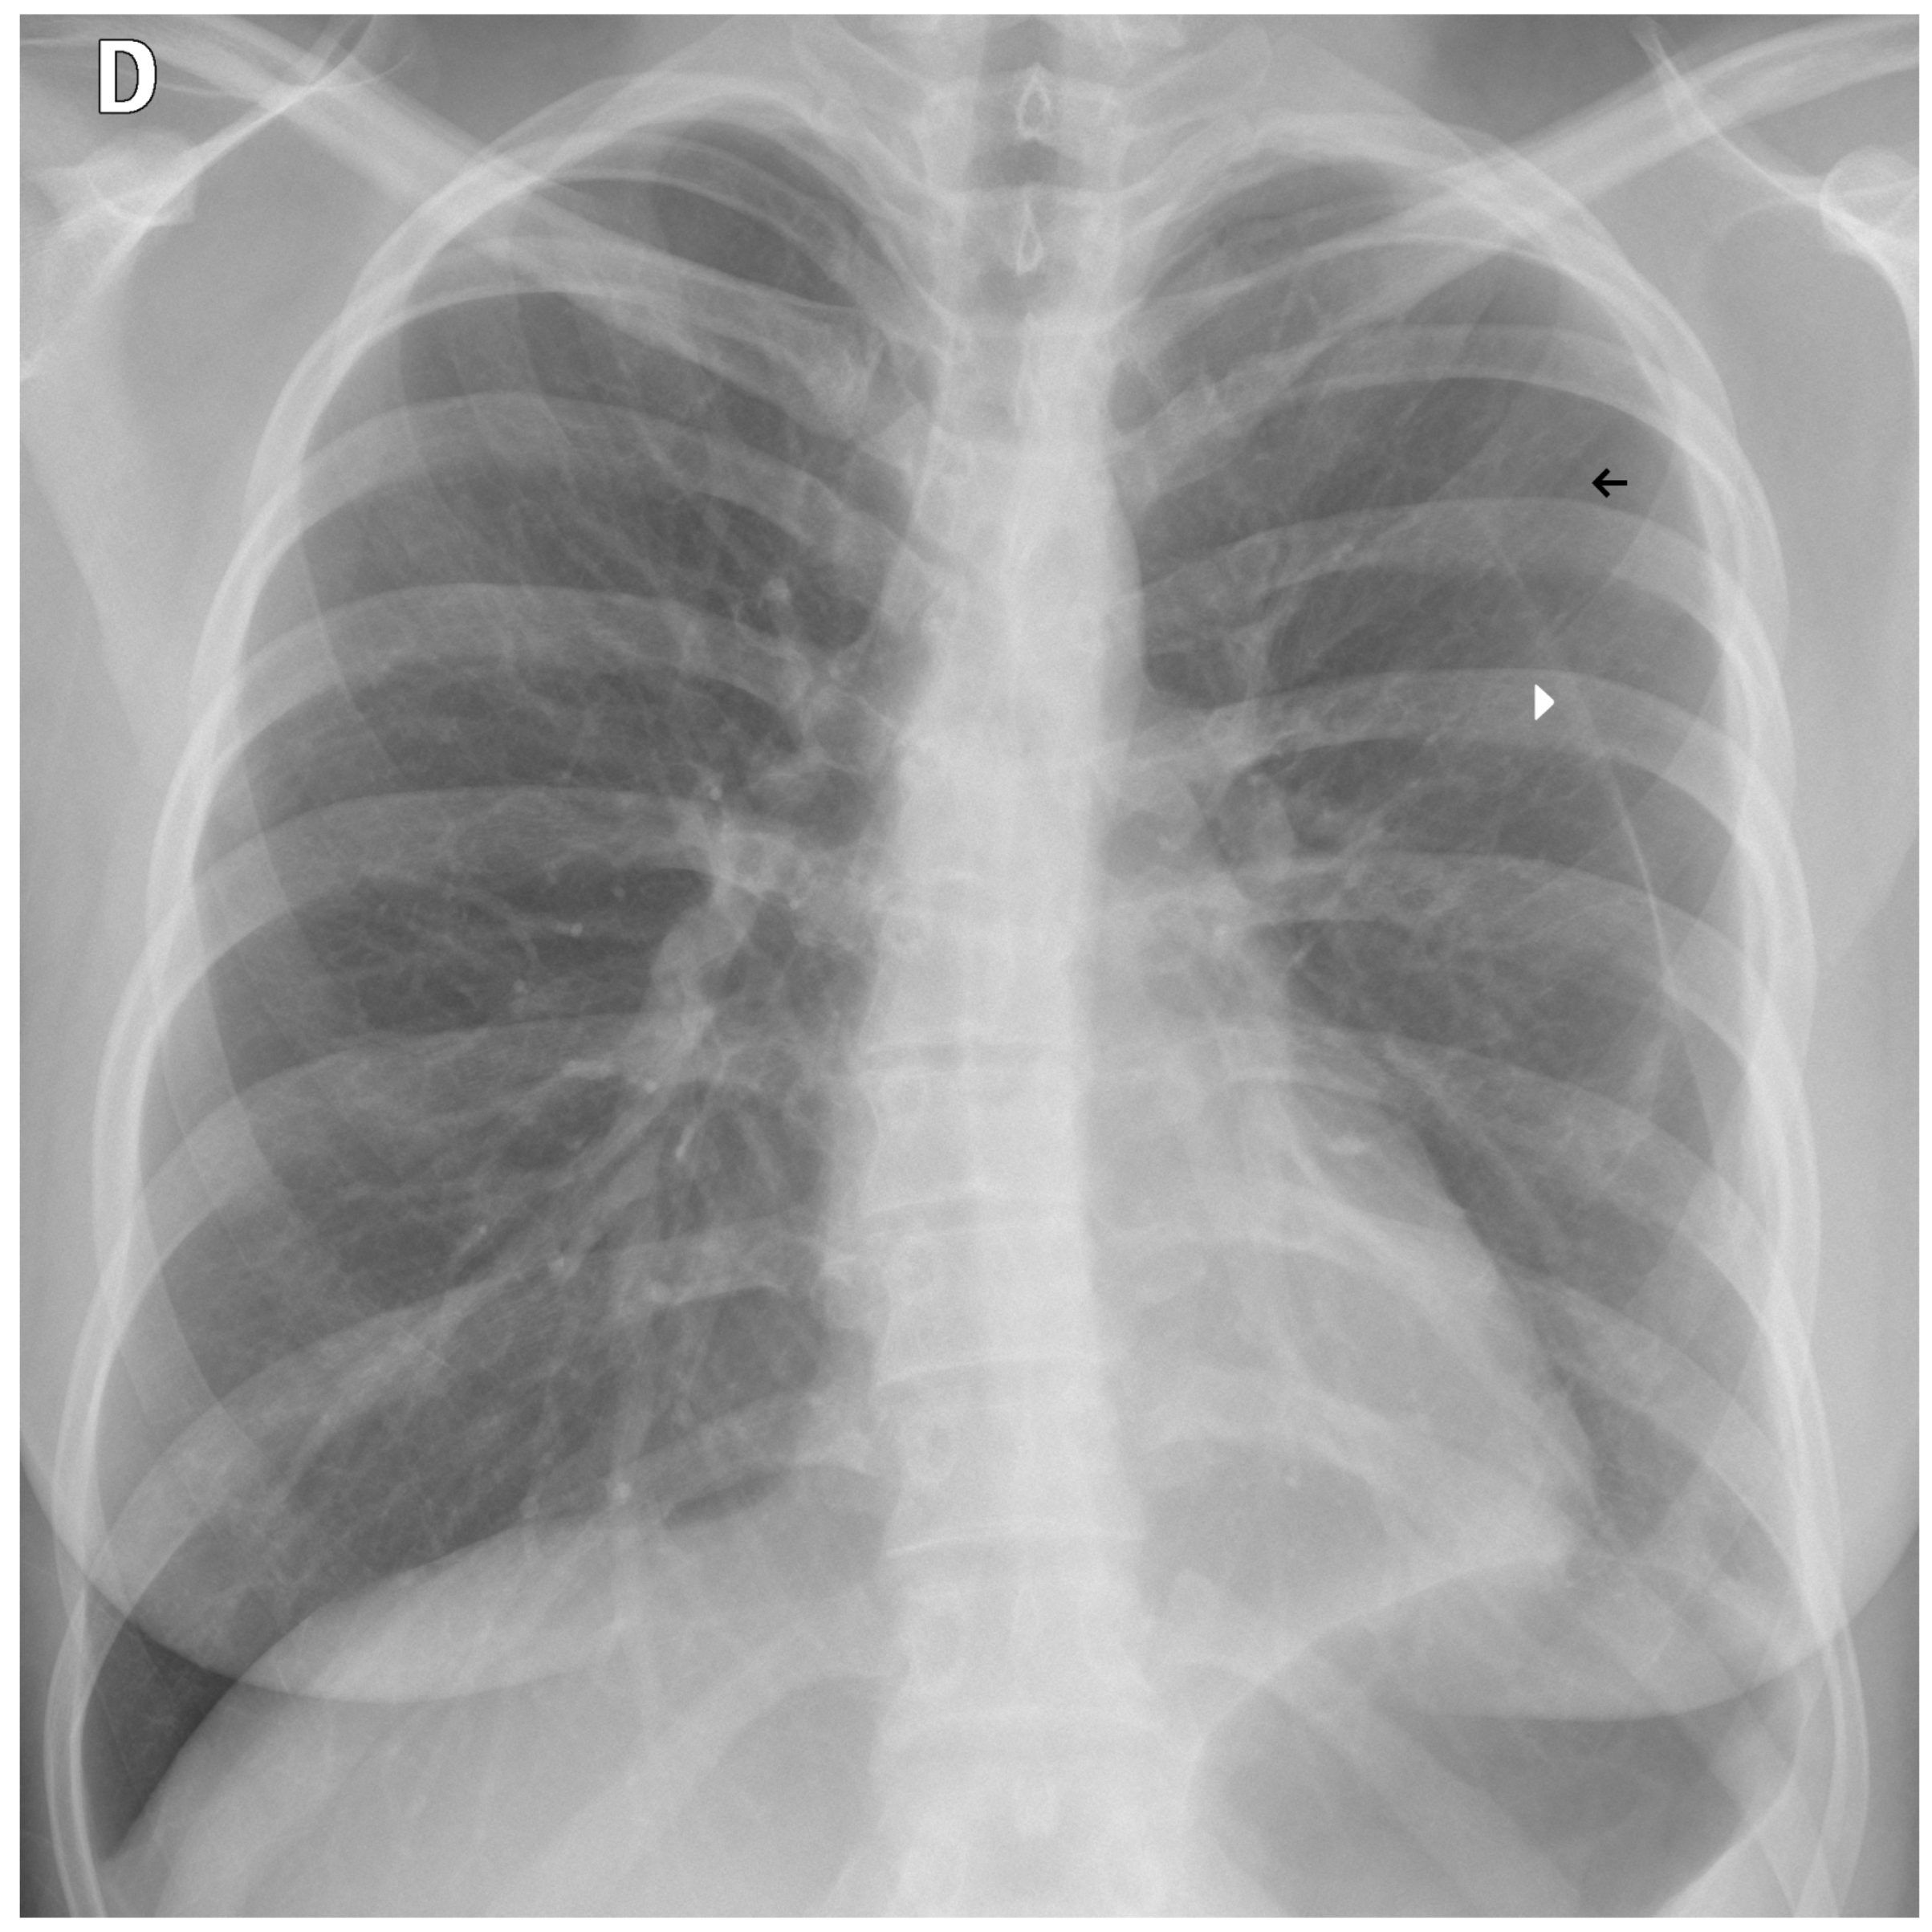

3.4. Clinical Workflow

As previously stated, clinicians implement TRIA in a clinical scenario. Upon image acquisition, CXRs are automatically forwarded from the institution’s PACS to the TRIA server. The algorithm processes the study and sends its findings—including the classification derived from the possibility ensemble and visual explainability aids, such as Grad-CAM heatmaps—directly back to the PACS. These results are then displayed to the radiologist within their standard viewer, alongside the original image (Figure 12). This seamless integration embeds the entire analysis within the patient’s study, enabling immediate worklist prioritization and concurrent review by the attending physician.

Figure 12. A real-world example of the TRIA system’s clinical integration within a commercial Picture Archiving and Communication System (PACS) viewer. The viewer displays the original posterior-anterior CXR (top left), the generated external contour image (top right), a heatmap visualization (bottom right), and the dedicated AI results panel (bottom left), which shows the possibility assessment and processing timestamps.